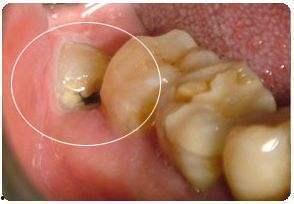

在正式进入手术室之前,你可能会在网络上看到很多关于拔智齿前的准备工作。首先,医生会给你做全面的口腔检查,确保你的智齿位置合适,拔除难度不大。他们会给你讲解手术过程,让你对即将发生的事情有个大致的了解。

别急,让我带你一探究竟。在拔智齿的视频中,你可以看到医生们是如何使用专业的工具,小心翼翼地分离智齿与牙槽骨的连接。他们会用牙挺、牙钳等工具,将智齿从牙槽骨中拔出。整个过程看似简单,但实际上需要医生们丰富的经验和精湛的技艺。